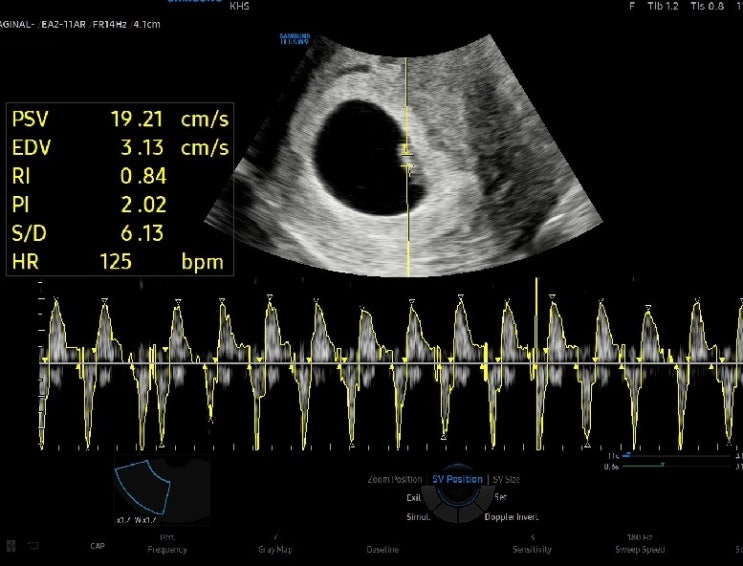

6주차, 난황 안녕! (태아보험가입과 산후조리원 계약까지)

일주일 만에 다시 병원을 방문했다. 비어있는 아기집이 자꾸 아른거렸고 심장소리도 듣고 싶고 괜히 걱정할...